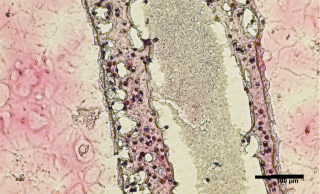

UBCVMarch 18, 2022 | Media release | Faculty & StaffUBC scientists discover how to 3D print testicular cells